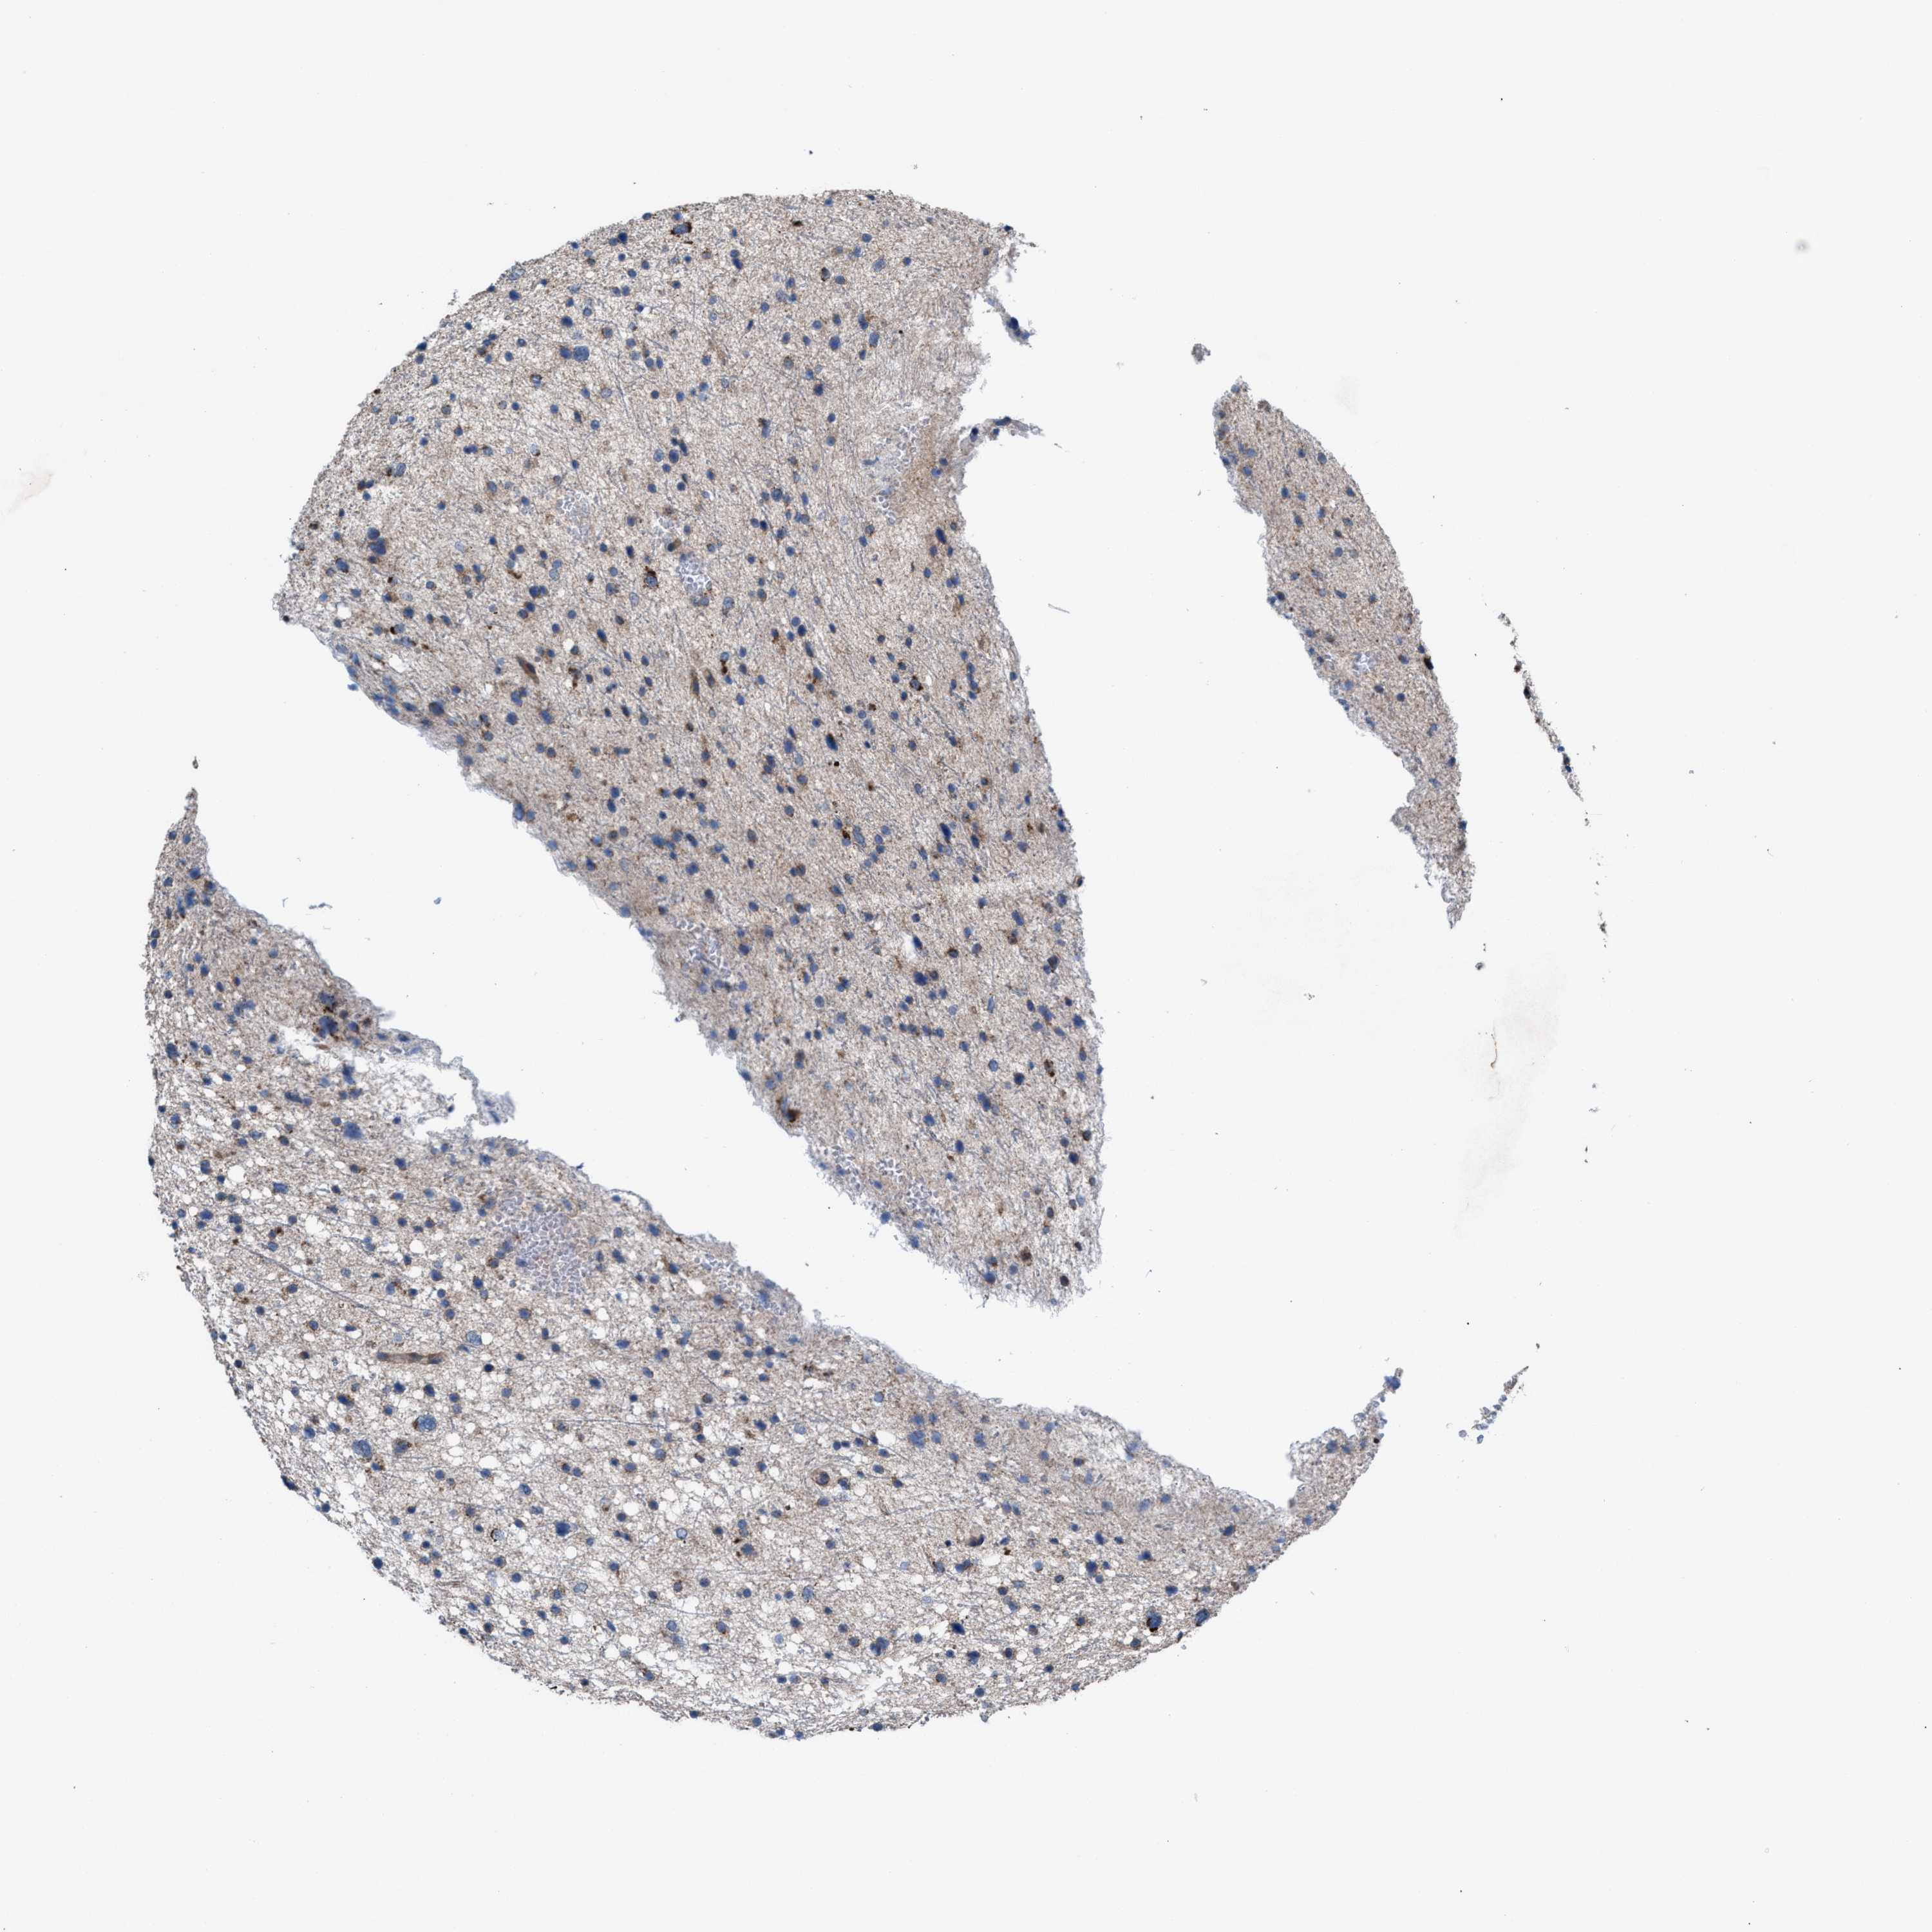

GLIOMA - Protein expressioni

A mouse-over function shows sample information and annotation data. Click on an image to view it in a full screen mode. Samples can be filtered based on level of antibody staining by selecting one or several of the following categories: high, medium, low and not detected. The assay and annotation is described here.

Note that samples used for immunohistochemistry by the Human Protein Atlas do not correspond to samples in the TCGA dataset.

Antibody stainingi

Antibody staining in the annotated cell types in the current human tissue is reported as not detected, low, medium, or high, based on conventional immunohistochemistry profiling in selected tissues. This score is based on the combination of the staining intensity and fraction of stained cells.

Each image is clickable and will lead to virtual microscopy that enables deeper exploration of all samples and also displays staining intensity scores, fraction scores and subcellular localization as well as patient and tissue information for each sample.

Antibody HPA021598

Staining

High

Medium

Low

Not detected

Intensity

Strong

Moderate

Weak

Negative

Quantity

>75%

75%-25%

<25%

None

Location

Nuclear

Cytoplasmic/membranous

Cytoplasmic/membranous,nuclear

Glioma, malignant, High grade

Glioma, malignant, Low grade